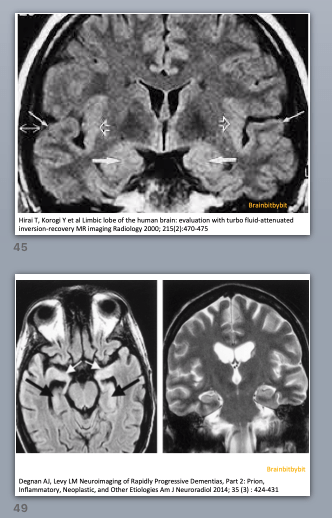

Figure 1. Coronal FLAIR image near the level of Monro’s foramen. The limbic structures (2) have a slightly higher signal intensity than the neocortex (3) because they are phylogenetically older and have a higher water content. Standard FLAIR images are not reliable for detecting abnormalities in the posterior fossa including the brain stem (1) and thalami.

*Note on figure 1: Standard FLAIR images are not reliable for detecting abnormalities in the posterior fossa and thalami.

The perceptibility of a lesion on MRI depends on the difference between the signal intensity of the lesion and the surrounding tissue (contrast) divided by the background noise.

The tissue in the brain stem is more heterogenous (gray and white matter intermixed) than supratentorial. Inflow of CSF and blood negatively influences the image quality of standard FLAIR images in the posterior fossa. By lengthening the inversion time and/or by performing 3D FLAIR, the visibility of infratentorial lesions can be improved.